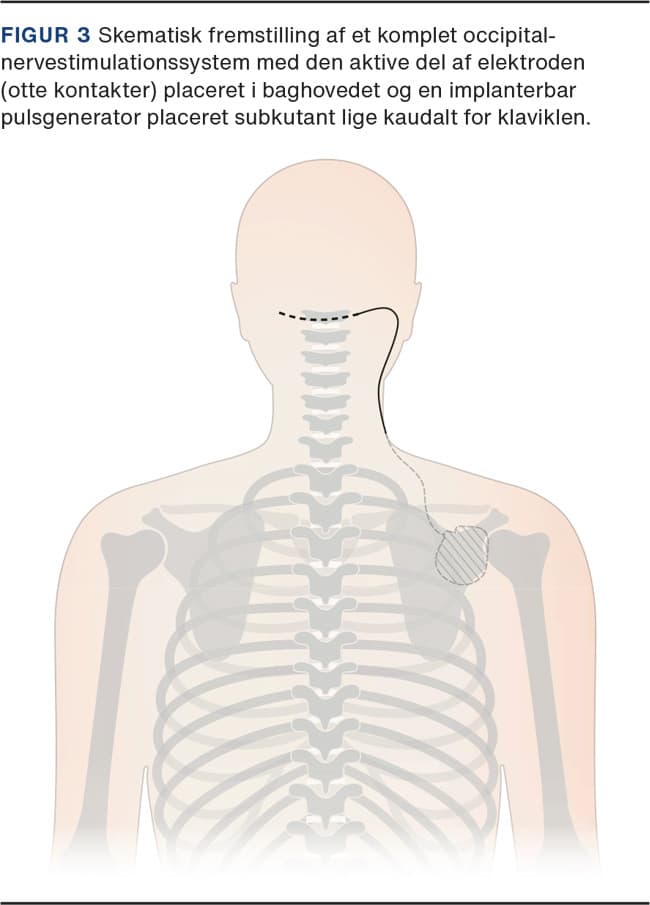

Behandlingen er en afart af PNS og bygger på 1-2 elektroder implanteret subkutant over nn. occipitalis major (Figur 3 og Figur 4). Virkningsmekanismen er ikke afklaret, men den mest udbredte hypotese er konvergens mellem disse nerver og autonome tråde til ganglion sphenopalatinum og ganglion trigeminale via centre i hjernestammen.

Occipitalnervestimulation

Hortons hovedpine (klyngehovedpine) er karakteriseret ved anfald af ekstremt intens, oftest unilateral hovedpine, der i de sværeste tilfælde kan være invaliderende og helt refraktær over for konventionelle behandlingstiltag. Occipitalnervestimulation (ONS) kan anvendes til behandling af svær Hortons hovedpine, hvor andre tiltag giver utilstrækkelig lindring [24].

ONS-behandling foretages altovervejende på AUH.